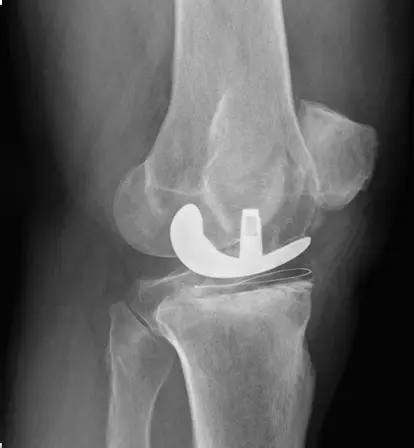

TKR surgery involves removing the damaged knee joint surfaces and replacing them with artificial implants that mimic natural movement. Robotic assistance may be used for precise implant alignment, enhancing joint stability and function.

- Accurate implant alignment with robotic assistance

- Restoration of knee stability and function

- Ensuring long-lasting joint durability